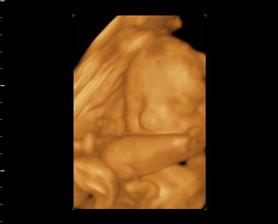

My a náš prvý očakávaný anjelik

Po roku dlhého skúšania sa nám konečne podarilo...Sme s manželom veľmi šťastní a nevieme sa našeho prvo-rodeného bábatka dočkať.